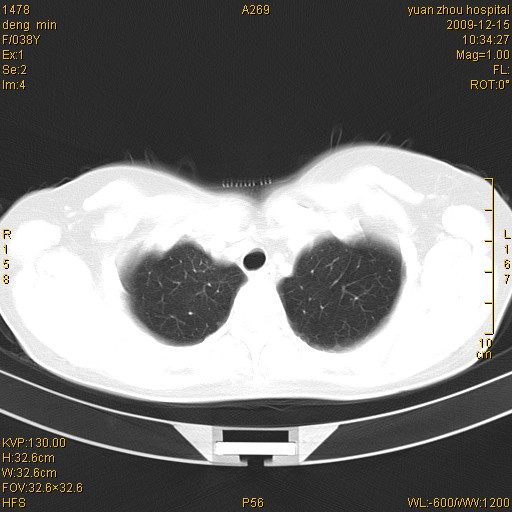

标题: CT23919:F38Y 咳嗽月余 [打印本页]

标题: CT23919:F38Y 咳嗽月余

右肺中下叶、左肺上叶舌段及左肺下叶支气管扩张合并感染。